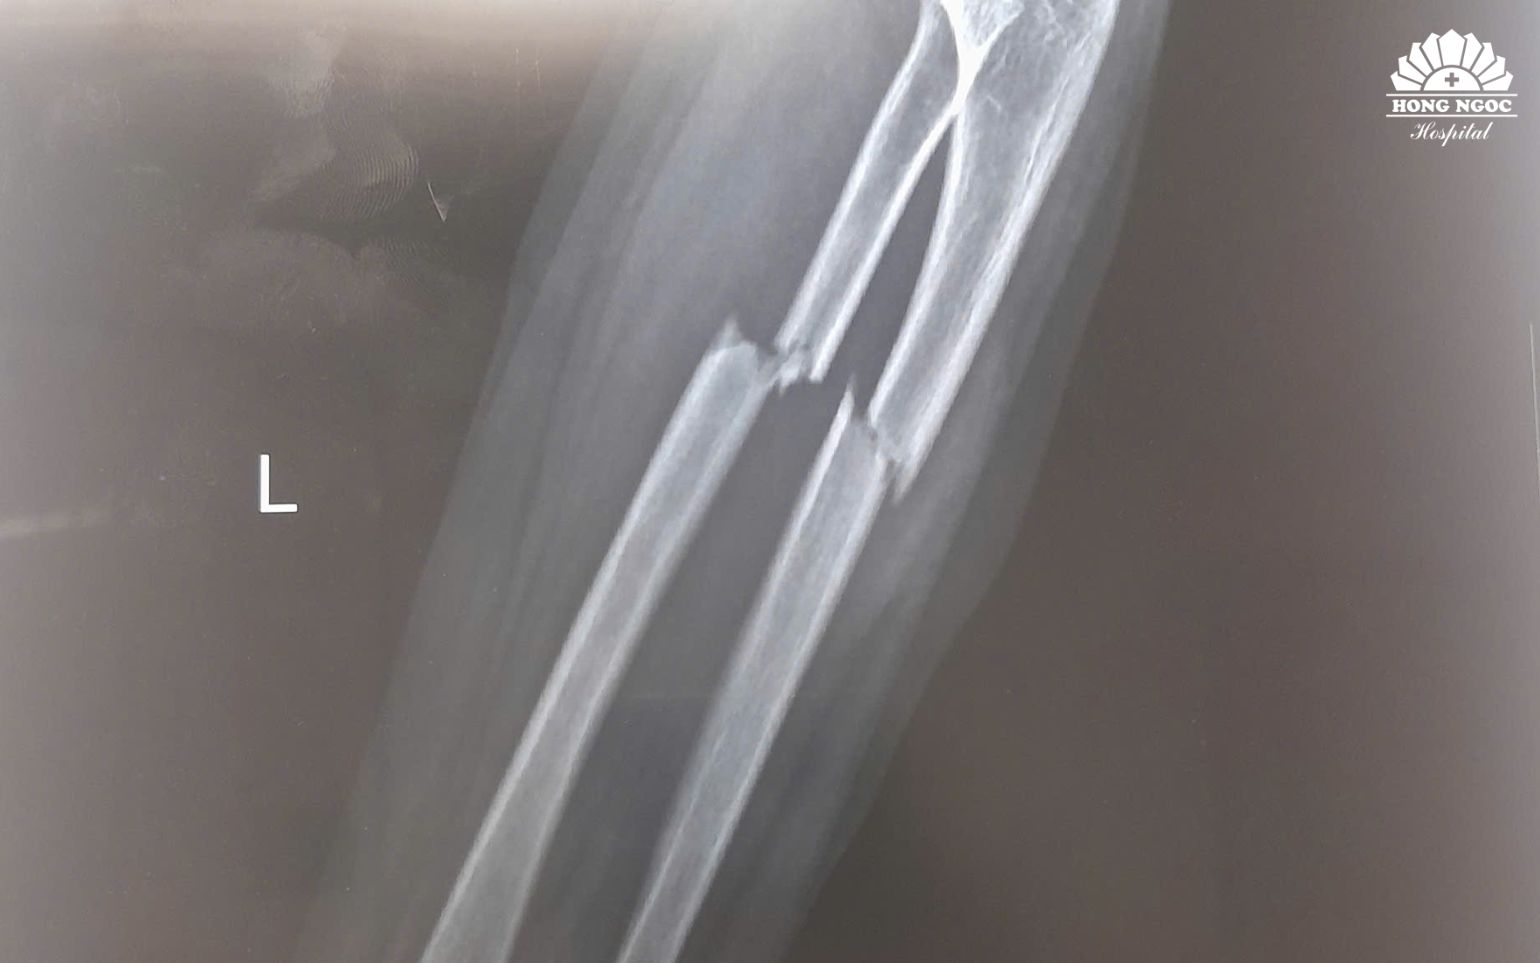

Bệnh nhi N.M.H. (7 tuổi, Bắc Ninh) đến thăm khám tại BVĐK Hồng Ngọc trong tình trạng đau nhiều vùng cẳng tay trái, hạn chế vận động sau khi đi xe đạp bị ngã. Kết quả chụp X-quang cho thấy bé bị gãy kín 1/3 trên cả hai xương cẳng tay trái (xương quay và xương trụ), có mảnh xương di lệch.

Gãy kín 1/3 trên hai xương cẳng tay trái gây đau, hạn chế vận động